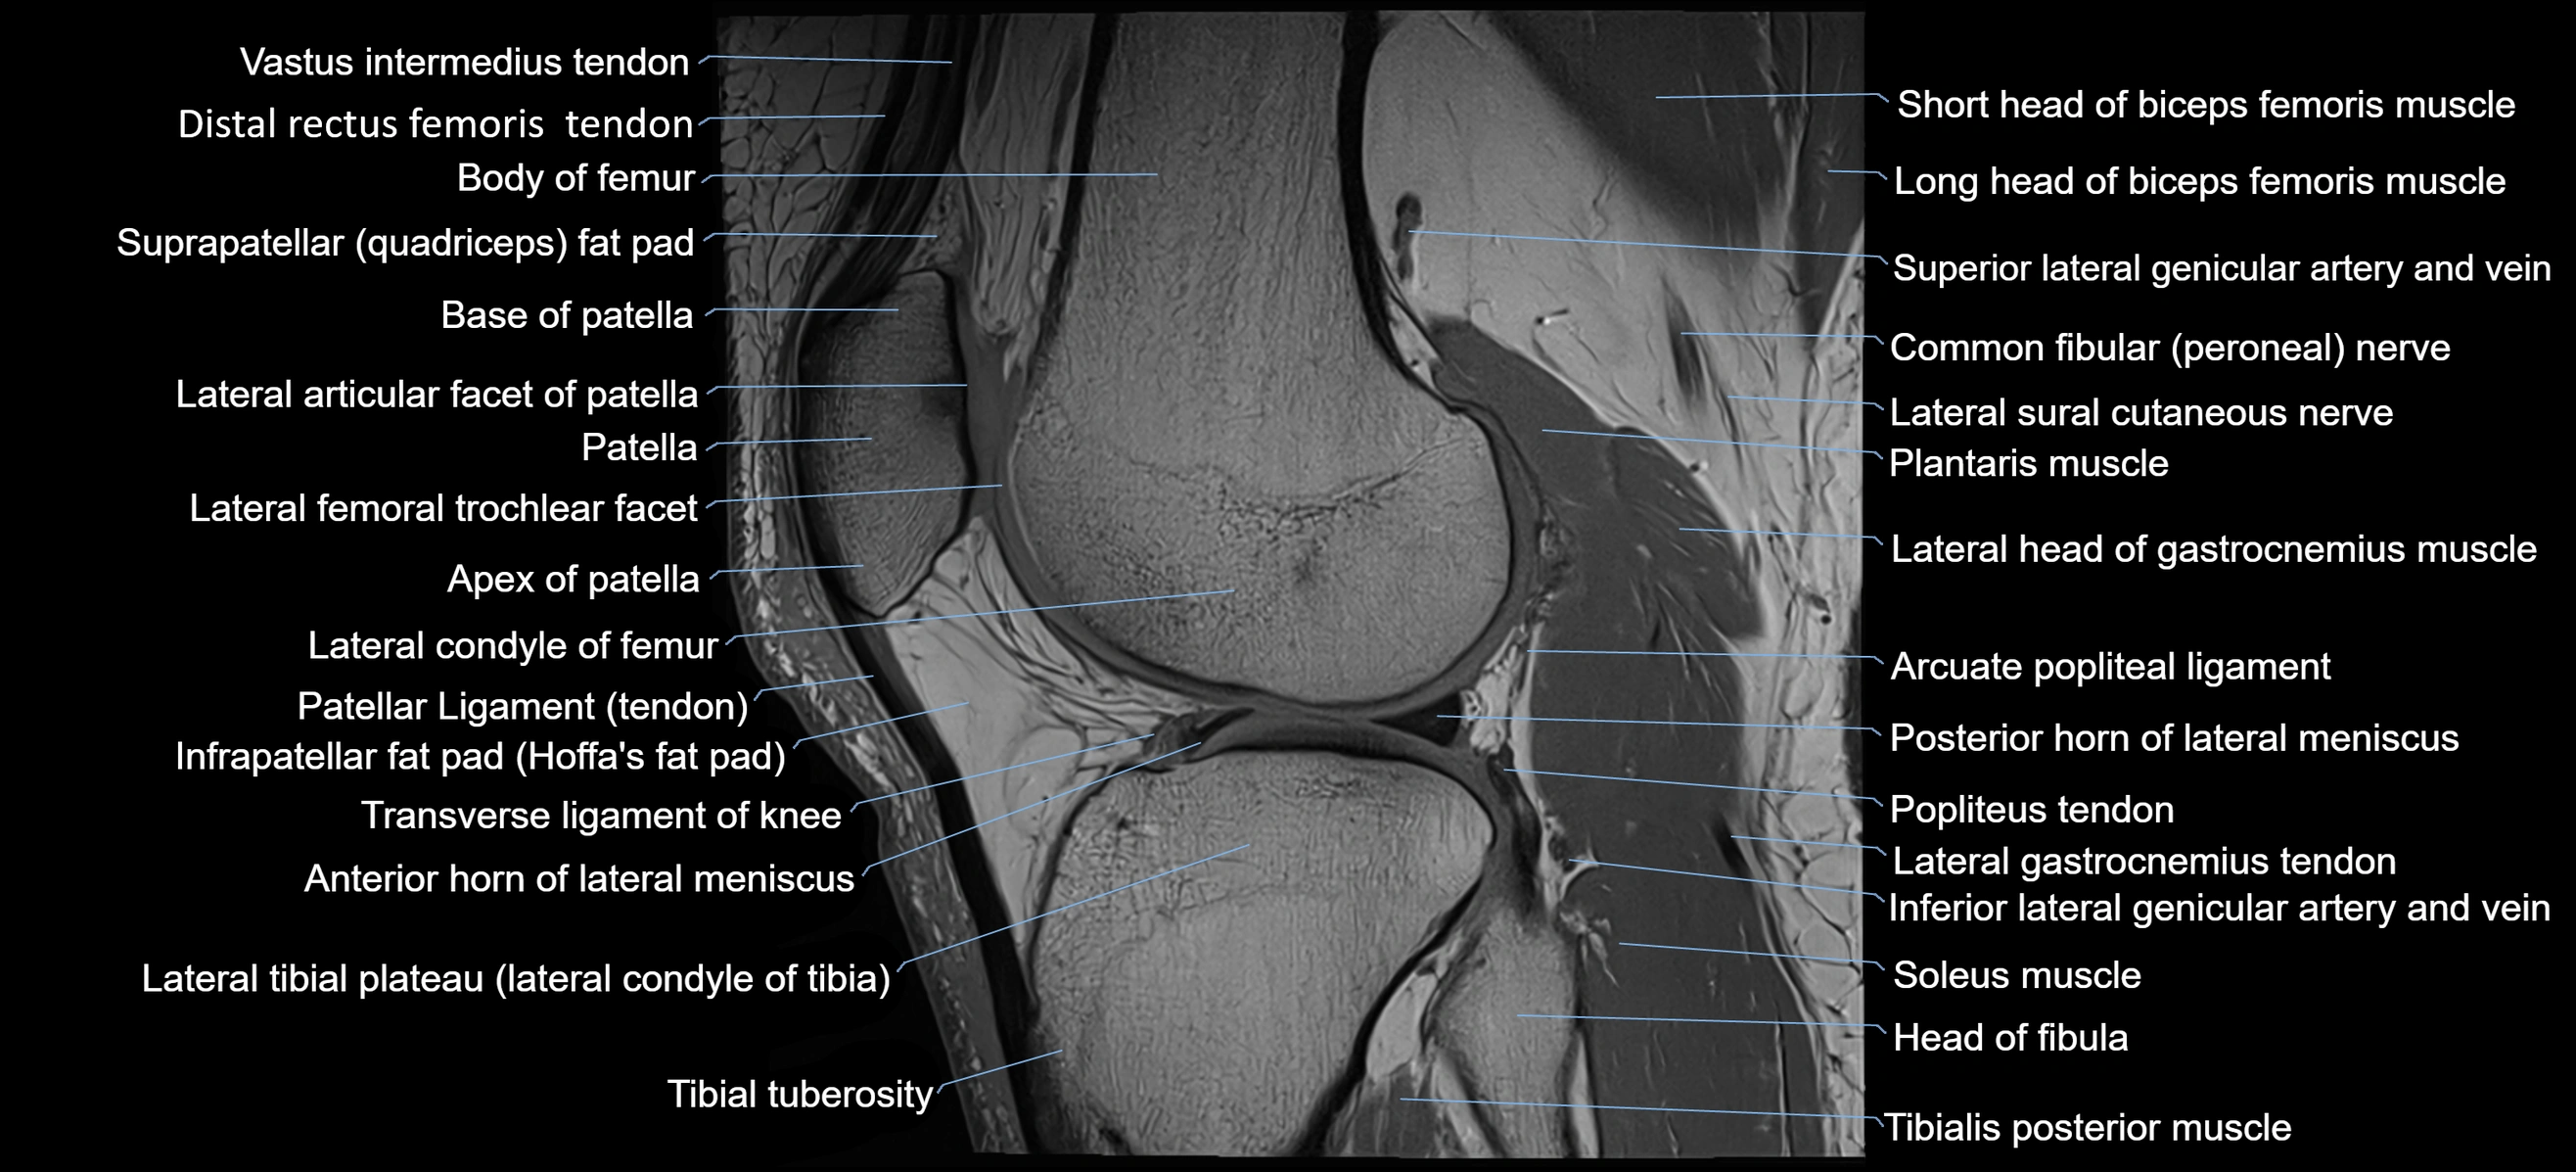

- Patellar tendon (patellar ligament)

- Popliteus tendon

- Posterior horn of lateral meniscus

- Transverse ligament of knee